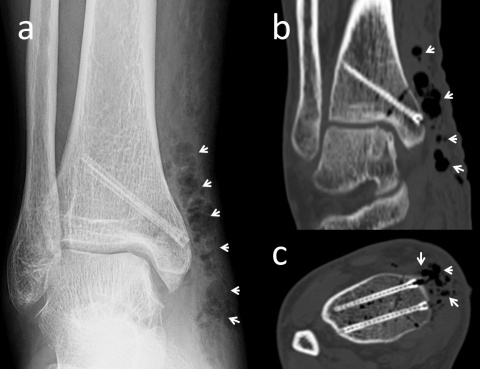

Magnesium-Kompressionsschrauben. (a) Mediale Spunggelenksfraktur

(b) Kahnbeinfraktur (c) Radiuskopffraktur (d) Distale Radiusfraktur (e)

Laterale Spunggelenksfraktur (f) Fingerfraktur (g) Tillaux-Fraktur im

Jugendalter (h) Abriss des hinteren Kreuzbands (ı) Capitulum-humeri-

Fraktur

Die Mg-Kompressions-Schraube MAGNEZIX® CS kann für eine ganze Reihe unterschiedlicher Indikationen in der orthopädischen und der Trauma-Chirurgie eingesetzt werden (Abbildung 1): grundsätzlich ist sie geeignet für die Versorgung von Frakturen und Pseudoarthrosen sowie Arthrodesen kleiner Knochen, im Speziellen Kahnbeinfrakturen, Abrissfrakturen, Sprunggelenksfrakturen, intraartikuläre Frakturen der Fußwurzel- und der Mittelfußknochen, der Handwurzel- und Mittelhandknochen, Bunionektomien und Osteotomien am Fuß oder Knöchel, Arthrodesen kleiner Gelenke (z. B. Phalangen), Patella-Frakturen, distale Ulna- und Radiusfrakturen, Radiuskopffrakturen und intraartikuläre Frakturen des distalen Humerus [13].